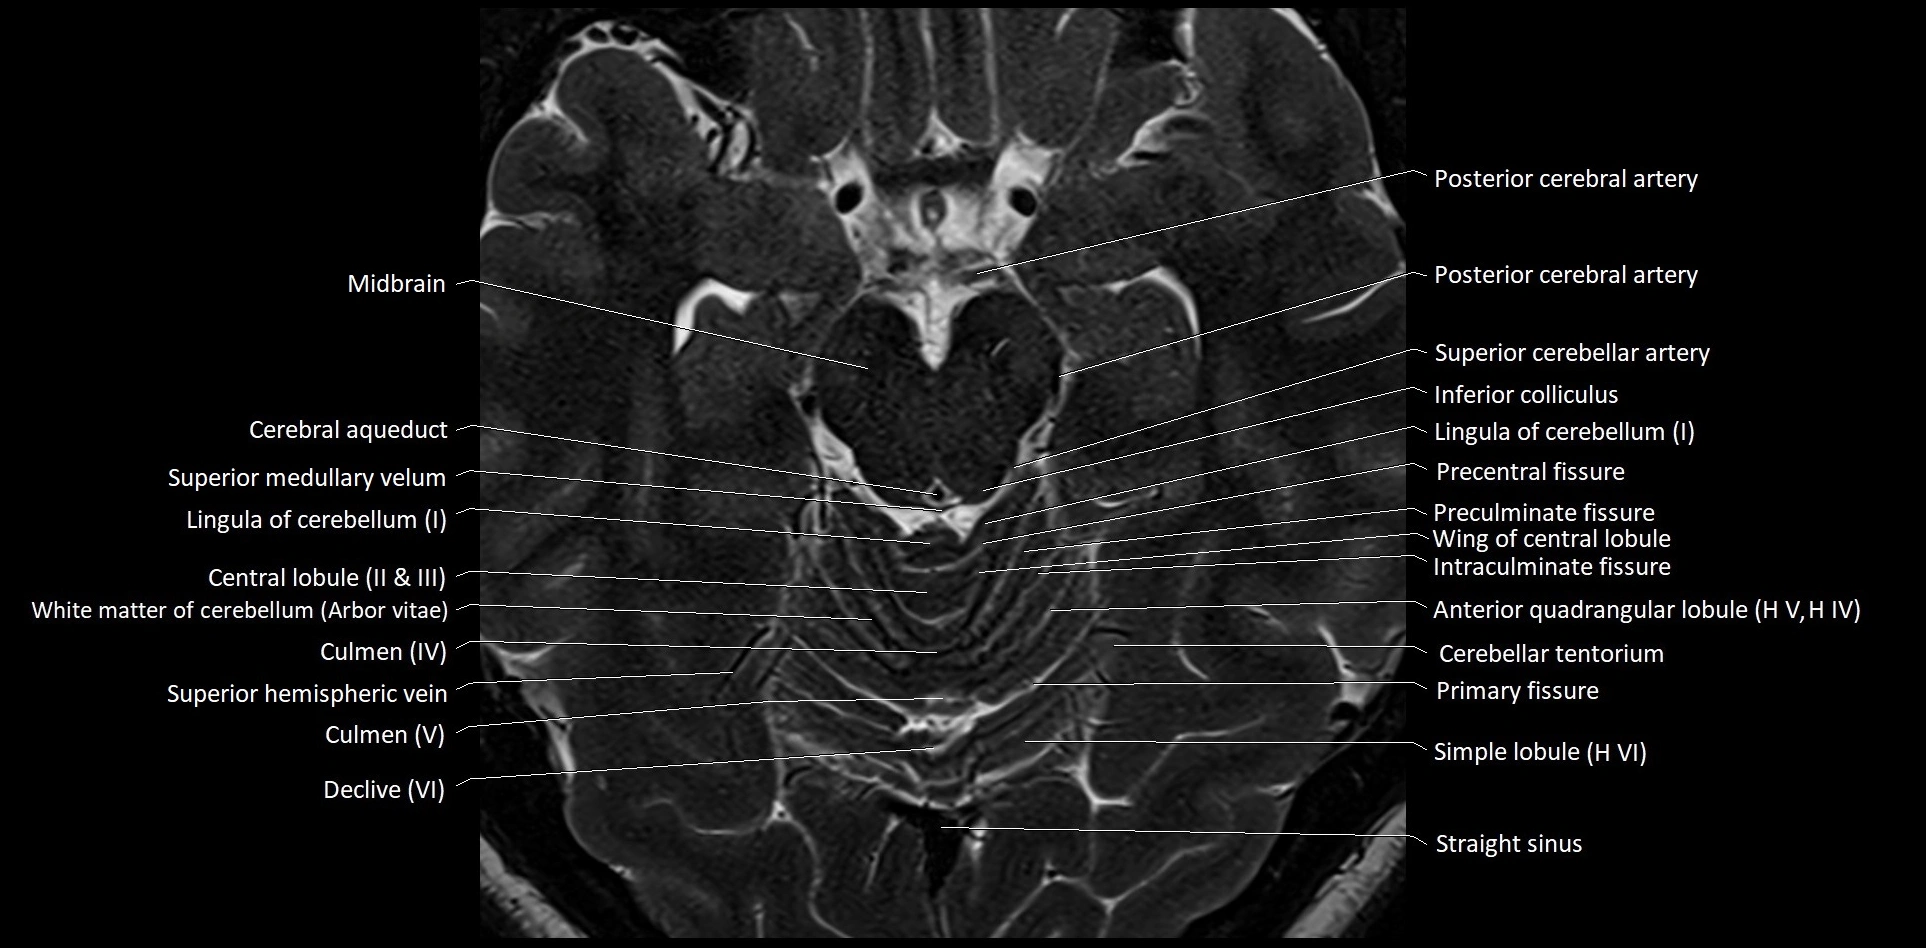

MRI images